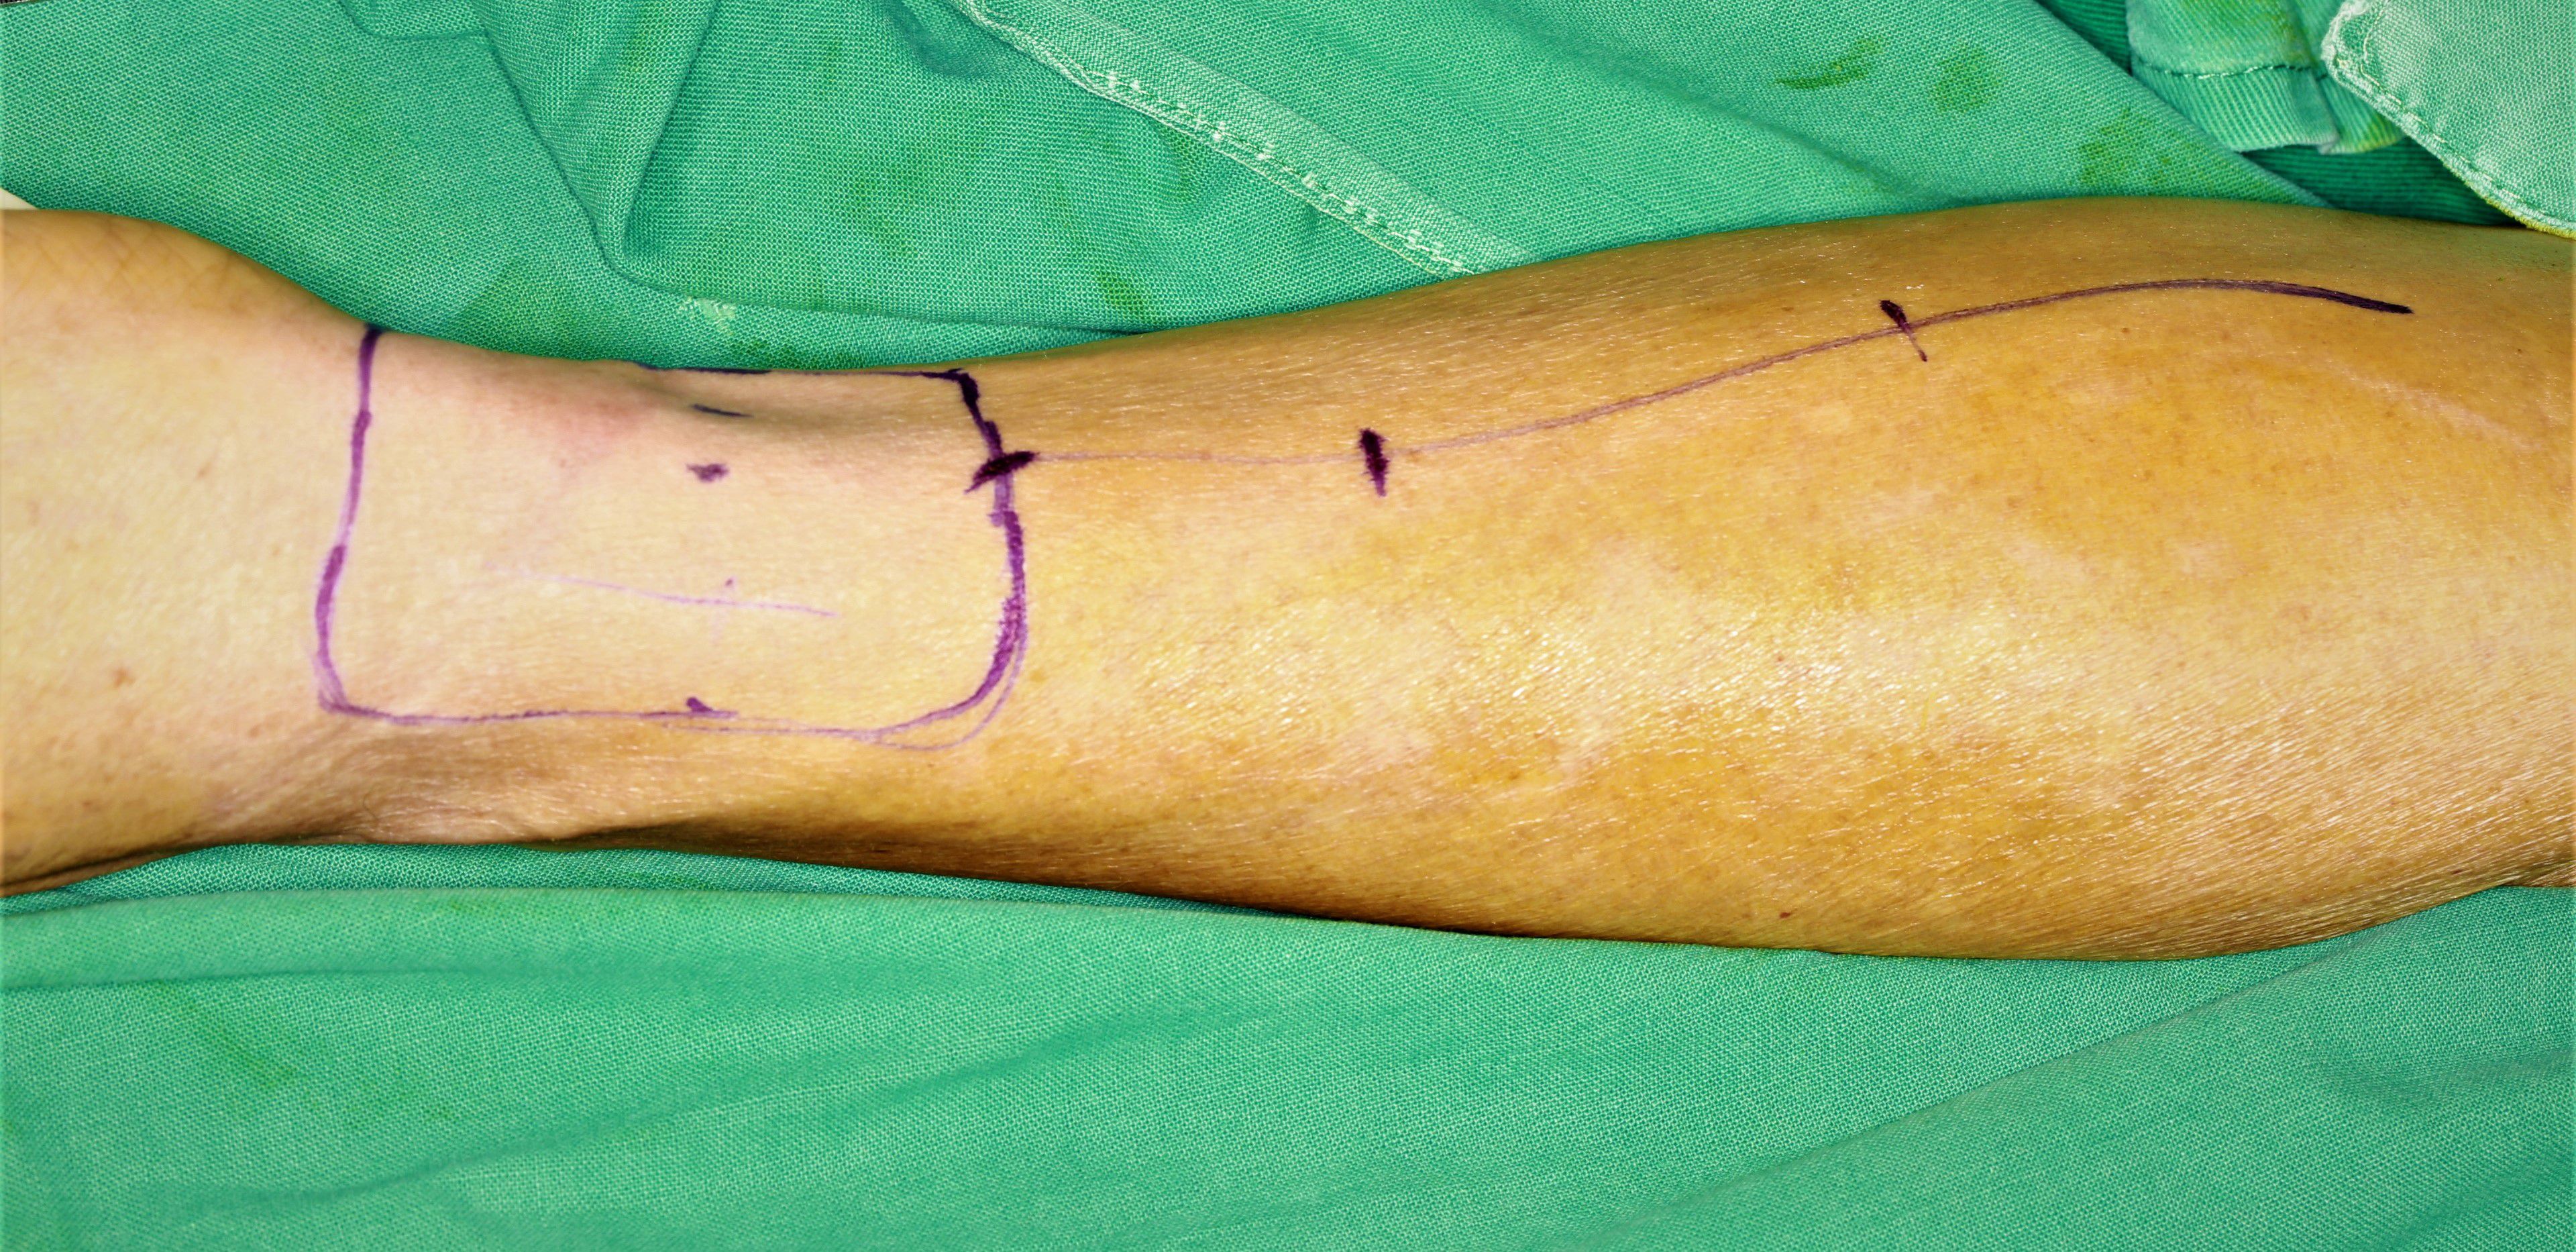

一、头颈部恶性肿瘤的综合治疗以及恶性肿瘤治疗后功能整复。针对各类口腔癌,尤其是中晚期口腔癌指定的个性化治疗方案。在进行肿瘤根治性治疗的基础上同期利用各种游离组织瓣移植修复完成缺损的一期修复。(图为前臂皮瓣与背阔肌皮瓣术前设计)